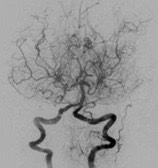

모야모야병은 뇌혈관, 특히 뇌로 혈액을 공급하는 내경동맥과 그 주변 주요 혈관이 점점 좁아지고 막히는 희귀 난치성 질환으로, 혈류가 줄어든 뇌는 부족한 혈액을 보충하기 위해 가느다란 미세측부혈관들을 새로 만들어냅니다. 이 작은 혈관들이 연기처럼 보인다고 하여 일본어로 ‘모야모야(안개·연기)’라는 이름이 붙었습니다. 소아부터 성인까지 폭넓게 나타나며, 특히 5~10세 어린이와 30대 전후의 여성에서 비교적 많이 발견되는 경향이 있습니다. 증상은 일시적 마비, 언어장애, 두통, 실신, 경련 등 매우 다양해 뇌졸중과 유사하거나 초기에는 가벼운 신경학적 증상으로만 나타나 진단이 늦어지기도 했습니다. 질환이 진행하면 허혈성 뇌졸중(뇌경색)이나 출혈성 뇌졸중 위험이 증가하여 반드시 전문적인 관리가 필요합니다. 아직 완전히 예방할 수 있는 방법은 없지만 조기 진단과 적절한 치료를 통해 뇌 기능을 보호하고 삶의 질을 유지할 수 있습니다.

모야모야병은 뇌기저부의 주요 혈관이 서서히 협착되고 막히면서 뇌혈류가 감소하는 만성 진행성 뇌혈관 질환입니다. 협착이 진행된 부위를 대신해 뇌는 생존을 위해 얇고 약한 혈관망을 만들어 혈류를 보충하려 하고, 이 새로운 혈관들이 촬영 영상에서 연기처럼 퍼져 보인다고 하여 ‘모야모야’라는 이름이 붙었습니다. 기전적으로는 내경동맥 말단부와 중대뇌동맥·전대뇌동맥의 기시부에 병변이 가장 잘 생기며, 시간이 지남에 따라 양쪽에 대칭적으로 나타나는 특징을 보였습니다. 이 질환은 단순한 혈관 협착이 아니라 진행성 변화이기 때문에 치료하지 않으면 혈류 부족이 심해지고 뇌 손상이 누적될 수 있습니다. 또한 뇌기능이 체력·호흡·체온 변화 등에 민감하게 반응하기 때문에 과호흡, 울음, 격렬한 운동, 감염 등으로 증상이 악화될 수 있습니다. 즉, 모야모야병은 시간이 지나면서 뇌혈류를 감소시키고 뇌졸중 위험을 높이는 질환이며, 평생 관리가 필요한 만성적 특성을 갖고 있습니다.

따라서 가족력이 있거나 의심되는 증상이 있다면 뇌 MRA·MRI 등의 정기검진이 도움이 되며, 조기 진단 시 치료 효과도 훨씬 높아집니다.